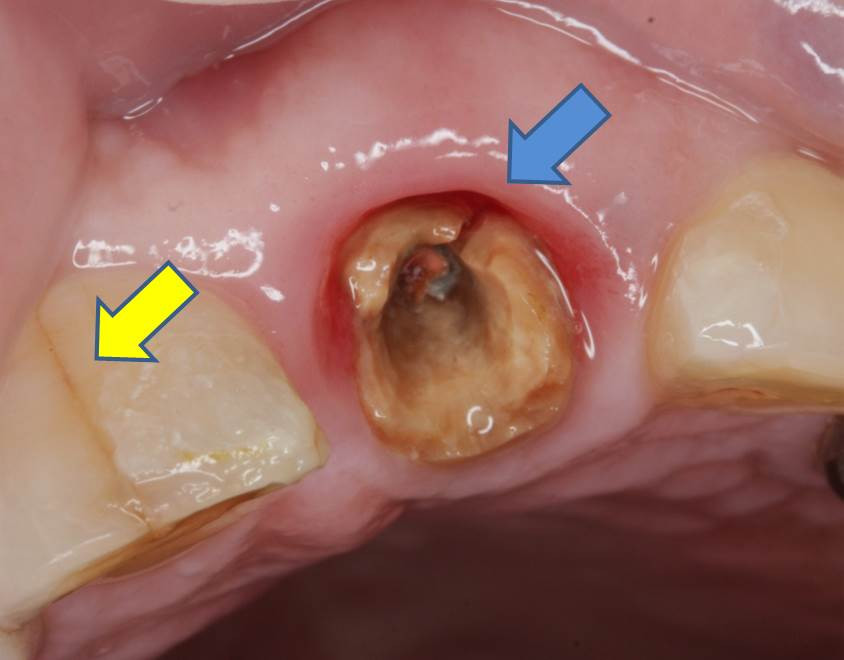

「治療して装着した被せ物が外れたので、かかりつけ歯科医院にて診てもらい再装着したが、調子が悪い」とのことでした。画像は冠を外した状態の写真です。

青矢印部分に破折線が見られ、‟歯根縦破折”という状態でした。破折線は根尖まで及んでいた為、『歯根縦破折を伴う慢性根尖性歯周炎』の診断の元、残念ながら抜歯術の適応であることを説明し、同意の上、施術となりました。黄矢印部分は隣の歯の歯冠部分ですが、ここにもエナメル質のマイクロクラック(破折線)が見られます。この患者様のような破折線が見られる場合には「咬合力(嚙み合わせる力)」が非常に強く、噛みしめで歯を失っていく傾向にあるため、注意が必要です。